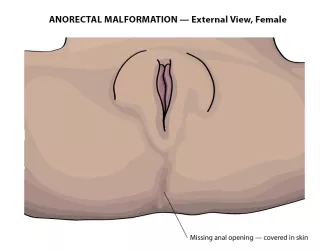

- In females, the intestine can join with the urinary system and vagina in a single opening, known as a cloaca.

The diagnosis is made by physical examination. If the anal opening is absent or in the wrong spot, it can be seen on examination. If there is stool coming out of the urethra, or vagina, instead of the anus, it will be visible. In females with anorectal malformation, careful examination of the vestibule (area between the labia) must be made to ensure separate openings of the urethra and vagina. In the males with imperforate anus, careful examination of the perineum is necessary to identify any abnormal passage of stool.